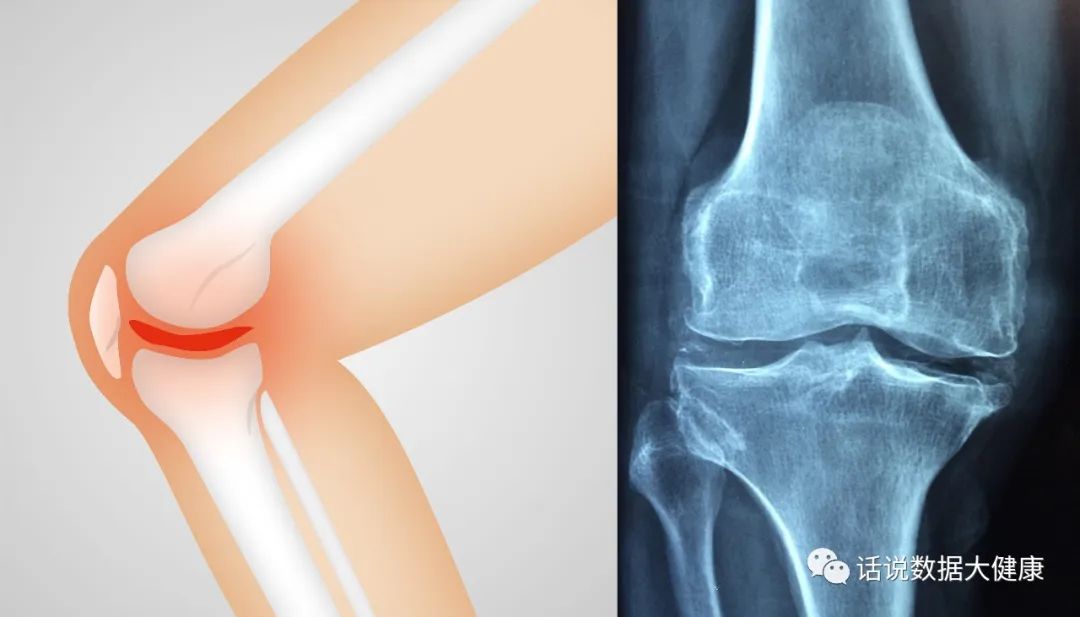

骨关节炎的特征是关节软骨破裂、软骨下骨重塑和滑膜低度炎症。比较遗憾的是,目前临床上还没有可用于骨关节炎的疾病缓解治疗方法。本号前期在《富血小板血浆,退行性关节炎的更好选择?》中也提到了富血小板血浆治疗骨关节炎效果并不明确。晚期骨关节炎的治疗措施主要是对症治疗和关节置换手术。

骨关节炎是中老年人疼痛和残疾的主要原因,严重影响着生活质量。骨关节炎并不是老年人的专属。越来越多超重、代谢异常或关节损伤的年轻人受到骨关节炎的困恼。